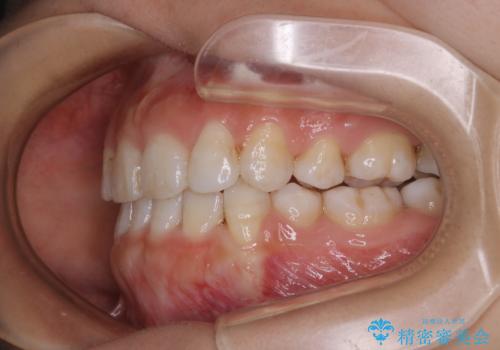

インビザライン単独での抜歯矯正治療

- インビザラインFULL

1日20時間以上、正しくインビザラインを使用して頂いたおかげで、ワイヤーに切り替えることなく矯正治療を終了することが出来ました。抜歯症例でしたが比較的短期間で見た目が劇的に改善し、大変喜んでいただけました。